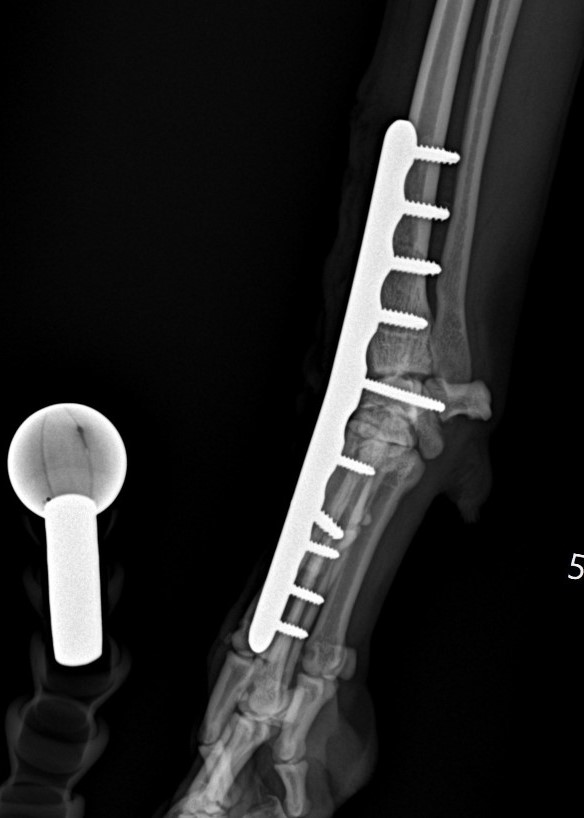

Artrodéza karpálního kloubu

Případy z praxe

Akutní

případ